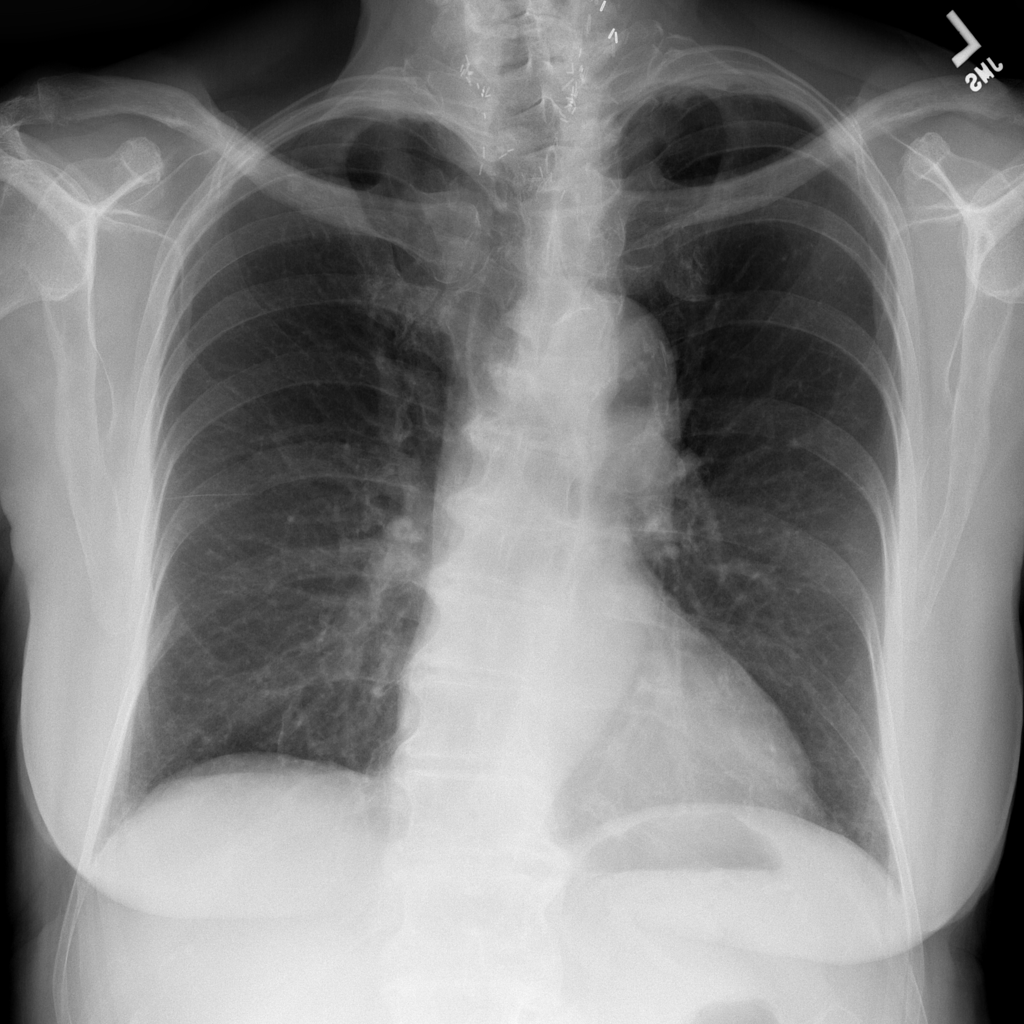

PAT-7F23 · IMG-000Emphysema

PAT-7F23 · IMG-000

PA